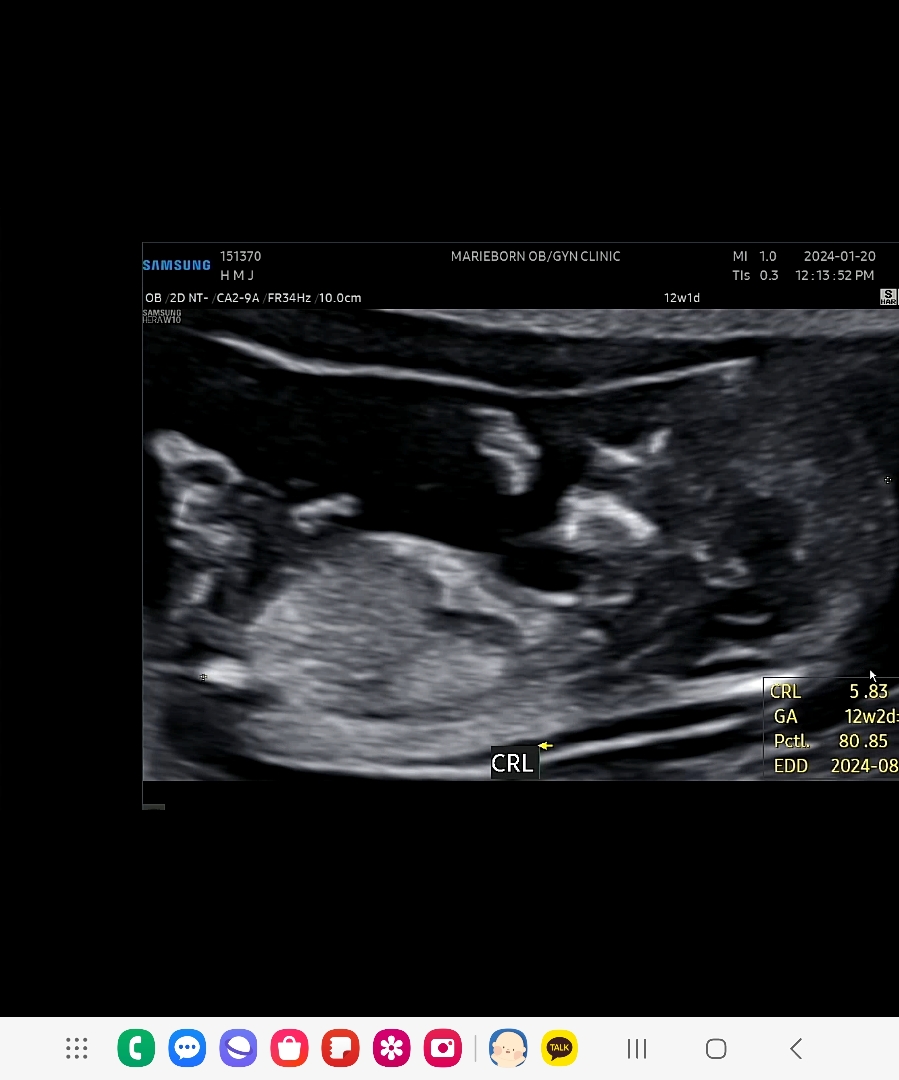

12주 각도법 보이시나요ㅠㅠ

너무너무 궁금한데 처음 녹화가 오류로 저장이 되지않아 짧게 다시찍어주셨네요.. 생식기가 보이지 않는거 같은데 부탁드려용..